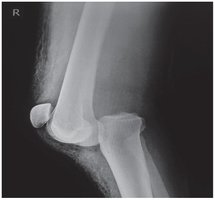

Dislocation and Arthritis

Dislocation: Complete displacement of a bone from its joint.

Osteoarthritis: Degenerative joint disease, bones in direct contact.